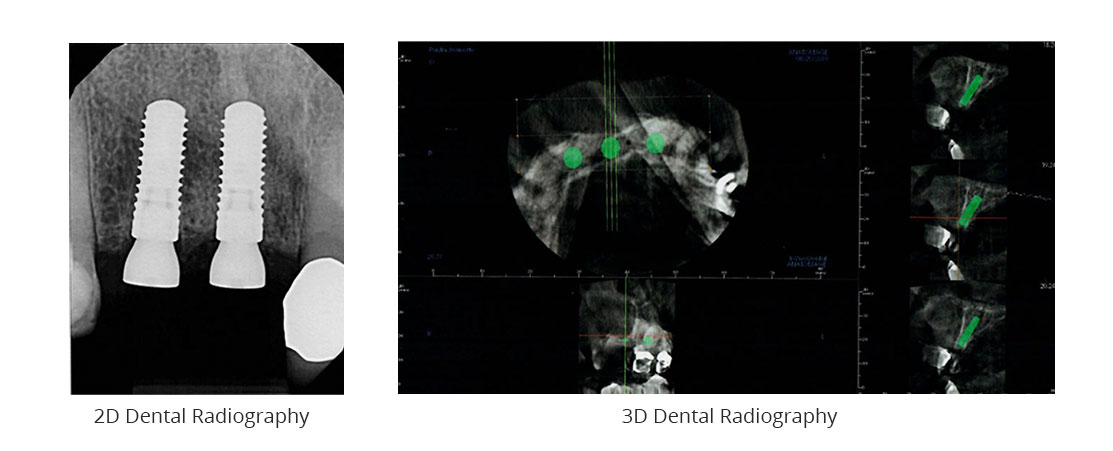

3D Dental Radiography

Radiography has been used in dental surgery for decades. As with most technological tools, several advances have been made in this field in recent years. For more than 10 years now, Dr. David’s clinic has been offering 3D digital radiography to its clients.

The quality of information: Thanks to this technology, the maxillofacial surgeon can collect a wealth of high-quality information to prepare your surgeries thoroughly and in advance. This data also helps to anticipate possible complications, thus helping to optimize results and healing.

A picture is worth a thousand words: During your consultations, your 3D X-rays are used by our team to explain to you efficiently and in detail the necessary interventions and the phases of the surgery. Reassuring and interesting, this step is an integral part of the clinic’s practices.